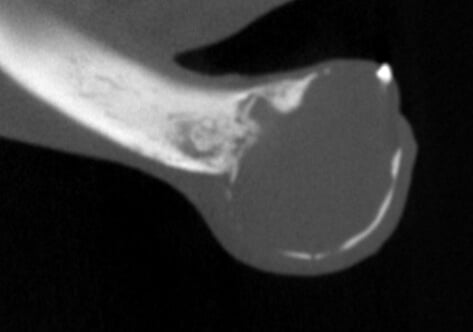

Bilateral rostral mandibulectomy to excise an oral mass that is suspected to be benign (not spreading) but locally invasive. Oral surgical removal of unerupted/impacted lower left canine tooth occupying the majority of the left mandible.

Cystic rostral mandibular swelling associated with unerupted 304. Adopted in Sept as intact male, estimate age 2. RDVM neutered and found mild swelling and unerupted 304 (lower left canine tooth). Swelling increased since adoption.

The canine tooth was not missing, but was impacted present in the middle of the left mandible. A tumor was present requiring removal of the tumor and associated impacted tooth.

We scaled, polished, performed 3D imaging and intraoral radiographs (x-rays), and confirmed the presence of an oral mass. The mass effect appears to have enlarged and extended to the lower right canine tooth.

As previously noted, the lower left canine tooth was unerupted and impacted into the center of the mandible. The cyst growth/mass effect has caused haphazard tissues to be present around all of the incisors.